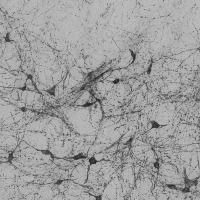

dopamine_th Computer Vision Project

The provided information seems to be insufficient to provide detailed use-cases. The model name, "dopamine_th" implies a possible connection to neurobiology, specifically, to dopamine neurotransmitters. Yet, the "th classes including th" part is unclear, as "th" is not a known term in either computer vision, biology, or bioinformatics domain. It might be a reference to certain classes in your data set, but without further context or clarification, it's challenging to provide accurate use cases. The image of a grey background also doesn't provide significant context. Could you please provide further details concerning this "th" term and more context related to the computer vision model?